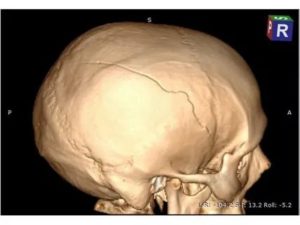

Томография. Двойной перелом.